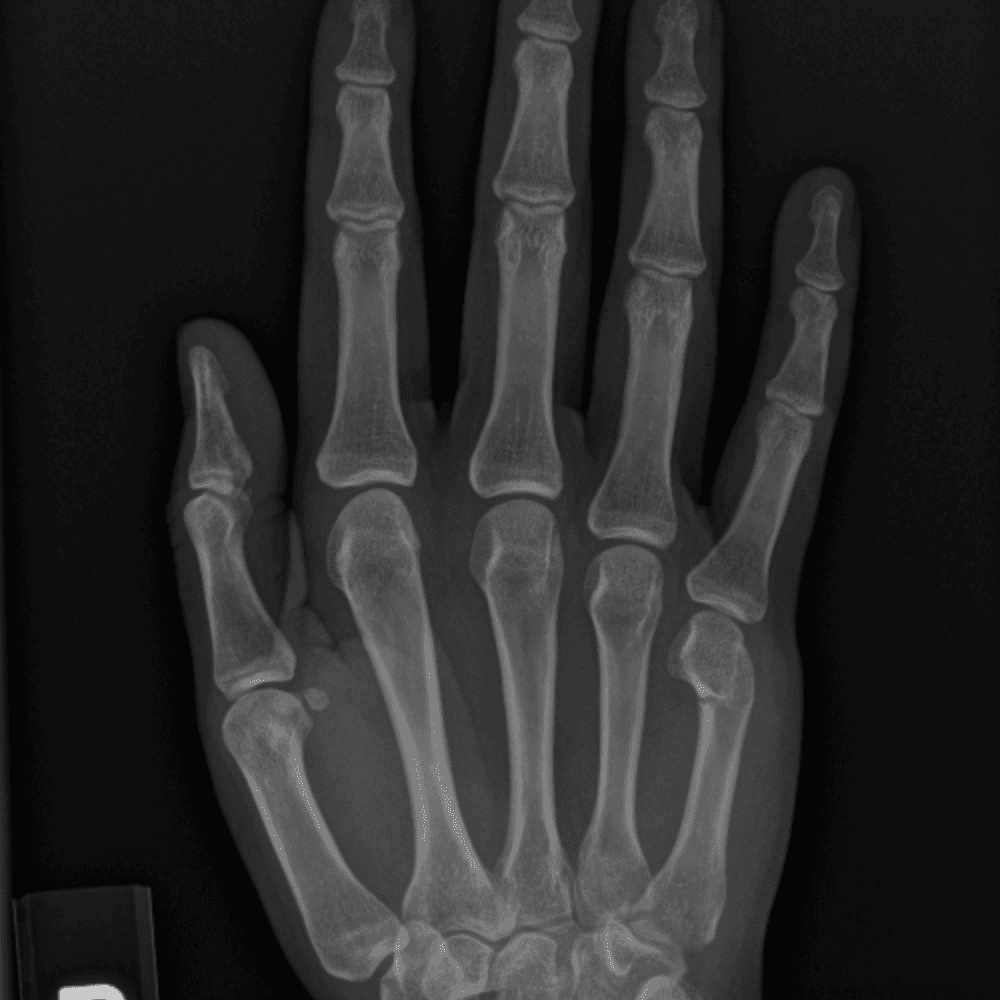

Simuliert den Dienst durch subtile oder schwierige Fälle und einige Normalbefunde.

30 Fälle